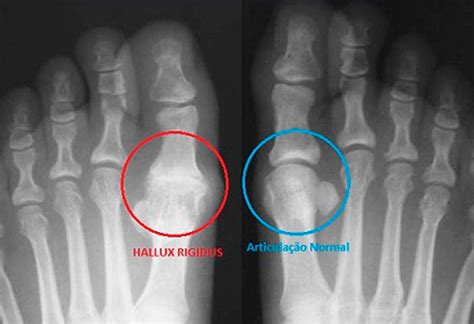

M70.1: Hallux Rigidus

Hallux rigidus is a condition characterized by stiffness and limited range of motion in the big toe joint. It can result from injury, arthritis, or wear-and-tear.

Hallux Rigidus